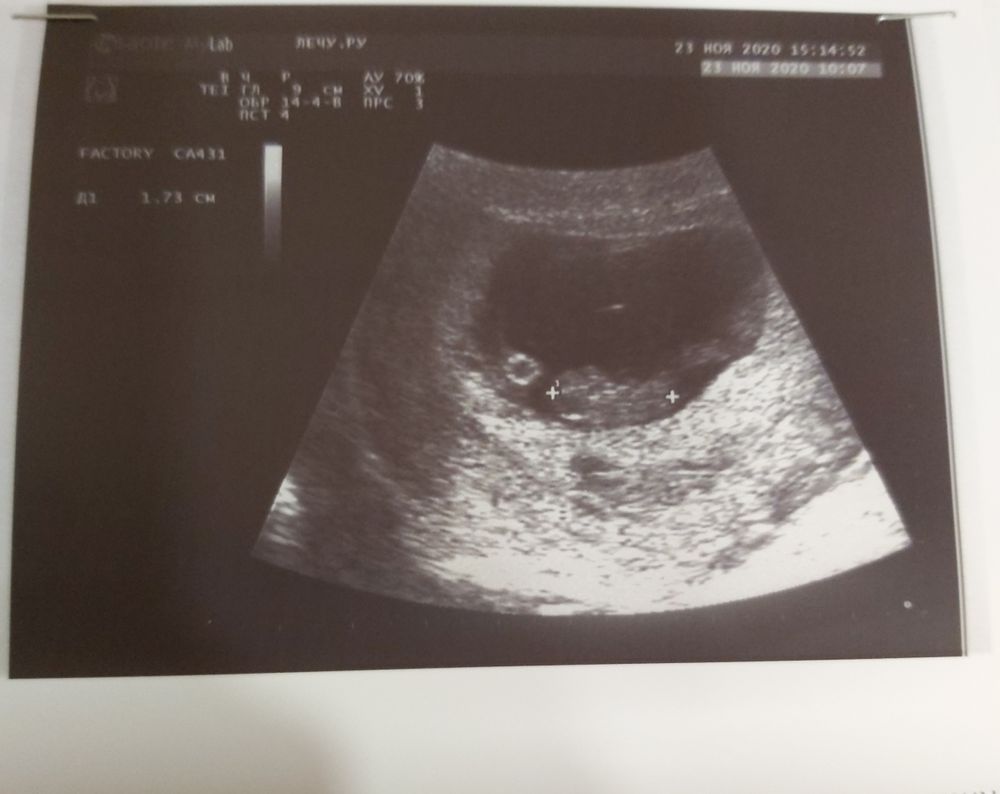

Я в шоке у нас получилось 😳 Моё УЗИ на акушерском сроке 5.4 недели